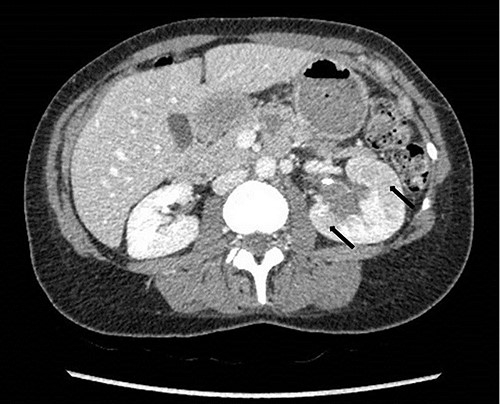

To investigate the bleeding source, she subsequently had a CT renal angiogram 3 days later that showed a narrow angle between origin of SMA and the aorta (Fig. 3) with multifocal areas of hypoattenuation throughout the left renal cortex (Fig. 4). It showed a compression ratio of 3.25 (diameter of pre-compressed vein =6.5 mm; diameter of compressed vein =2 mm) (Fig. 5).

Computed tomography on presentation showing multifocal areas of hypoattenuation throughout the left renal cortex (arrows).